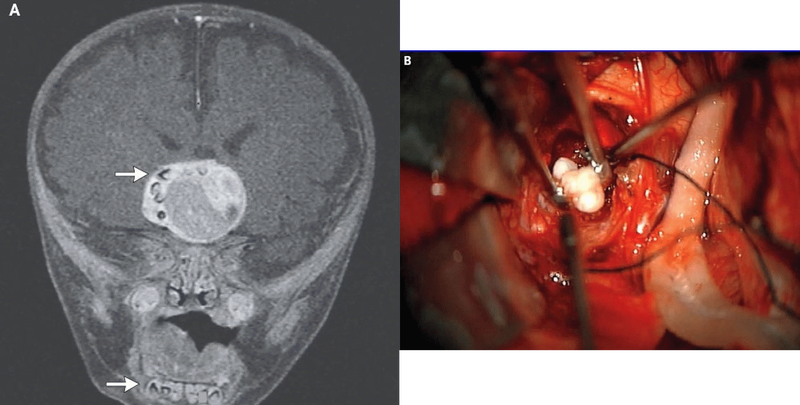

Врачи заподозрили неладное, когда голова ребенка начала расти значительно быстрее обычного. Томография головного

Краниофарингиома — это редкая врожденная доброкачественная опухоль, встречающаяся не чаще, чем у двух человек на миллион. Она развивается в случае некорректного протекания процессов формирования органов черепа. В процессе роста новообразования, в него вовлекаются ткани, которые в норме формируют зубы. Однако никогда ранее полноценных зубов в таких опухолях не находили.